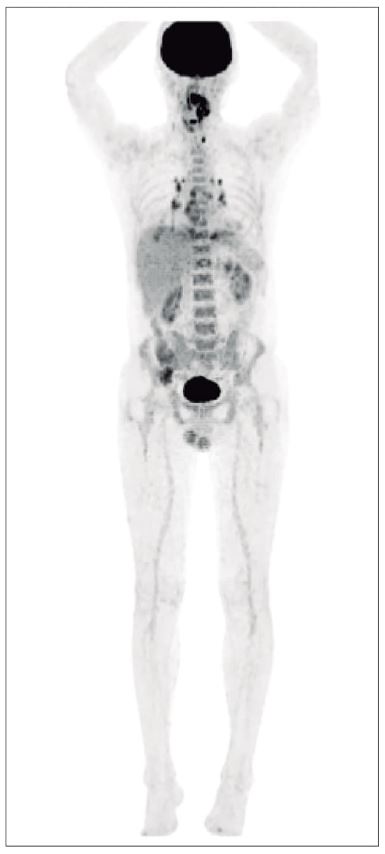

Gracias al desarrollo de compuestos dirigidos como el PSMA-11 y el PSMA-617, y al uso de técnicas avanzadas como PET/CT y PET/RM, se ha logrado una mayor precisión en la detección de células malignas, incluso en etapas metastásicas. Este artículo resume los principales hallazgos y aplicaciones clínicas descritas en el texto, con especial énfasis en los radiofármacos más relevantes.

Impacto de la imagenología PET/CT y PET/RM en la estadificación y seguimiento

Las técnicas de imagenología molecular como PET/CT y PET/RM han revolucionado el abordaje del cáncer de próstata. Su combinación con radiofármacos permite:

- Mayor sensibilidad y especificidad en la detección de lesiones.

- Evaluación precisa de la extensión locorregional y metastásica.

- Seguimiento dinámico de la respuesta al tratamiento.